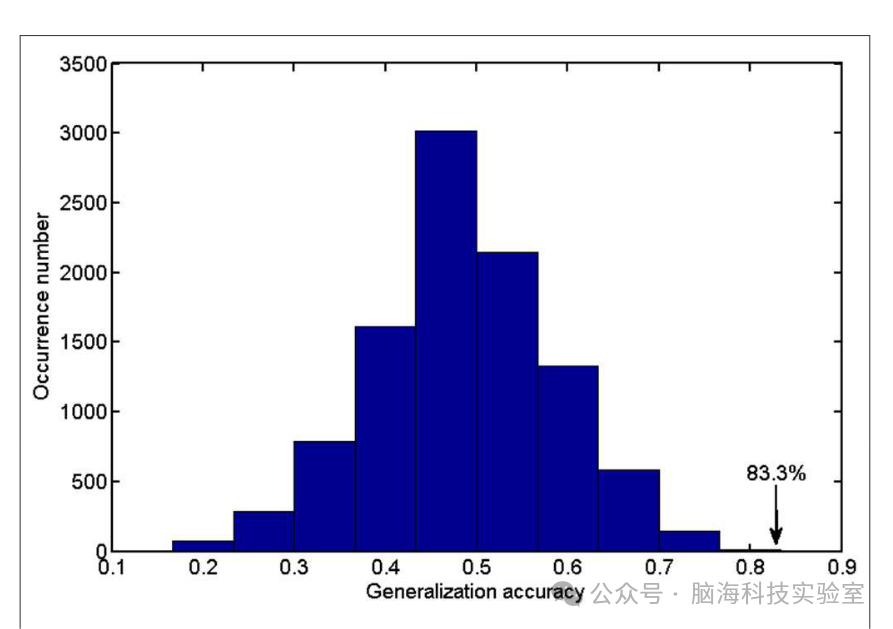

图2展示了基于不同数量的FA特征的准确率、敏感性和特异性的详细结果。当特征集的规模较小时,输入数据无法提供足够的信息来训练出一个可靠的模型;而如果特征集规模过大,输入数据中会出现冗余或不相关的信息,从而导致机器学习的性能下降。只有当选择了适当的数据集时,分类算法才能达到最佳性能。当选择特定数量(1,400到3,400之间)的特征时,可以获得最佳的分类准确率。因此,研究选择了排名前2,400(1,400和3,400之间的中间值)的特征作为最优特征。利用这些具有区分能力的特征,研究确定SVM分类器的准确率可以高达83.33%(敏感性=77.27%,特异性=88.46%,P=0.0001)。以泛化准确率作为统计变量,估计的置换分布如图3所示,表明分类准确率大于83.33%的概率非常低(P=0.0001),这表明研究的结果高度可靠。

图3